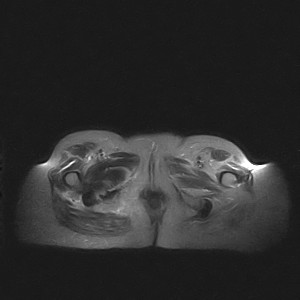

标题: MRI2691:读片病例2

我帮传的没看到病史!!!

图像太差了 1、右侧臀肌旁脓肿? 建议增强 2、左侧股骨头坏死并半脱位

1、左侧股骨头坏死并髋关节半脱位;

2、右侧臀肌感染,(可能褥疮所致)